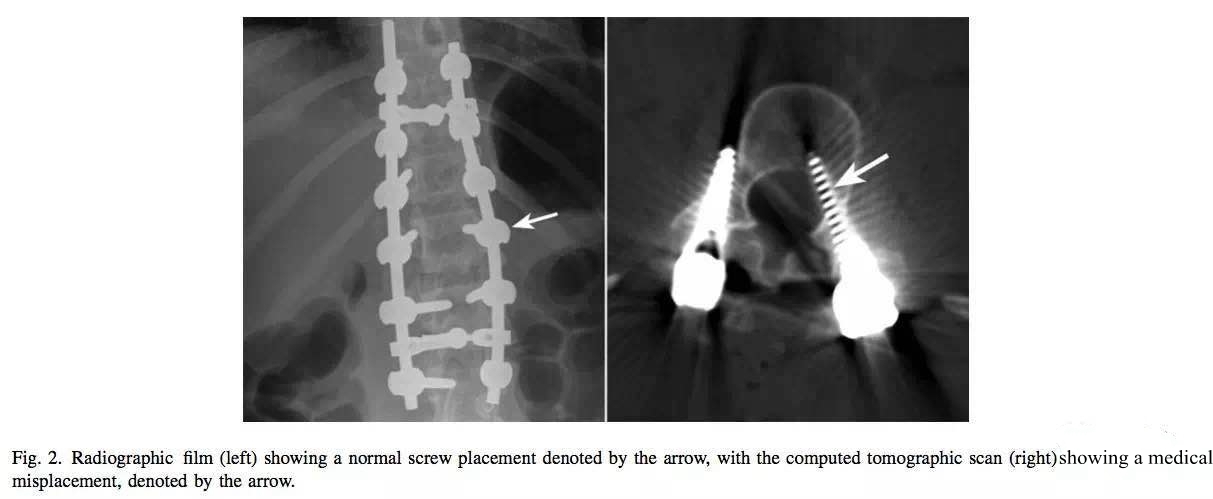

X线片显示钉道位置良好,但CT复查显示进了椎管。